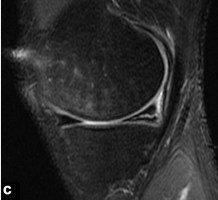

Le ménisque discoïde est une malformation congénitale rare du ménisque.Cette dysplasie méniscale touche presque exclusivement le ménisque latéral.Son diagnostic 'académique' en IRM repose sur la visualisation de la continuité des cornes antérieure et postérieure sur des clichés sagittaux en au moins 3 coupes consécutives de 5 mm d'épaisseur (Fig. 2).Ces résultats sont ajustés en fonction des paramètres partiels utilisés.

Figure 2 Ménisque latéral discoïde.Image sagittale pondérée en T1.Continuité des angles avant et arrière sur 3 profilés fixes consécutifs de 5 mm.Notez la dégénérescence myxoïde de la corne antérieure de ce ménisque discoïde.